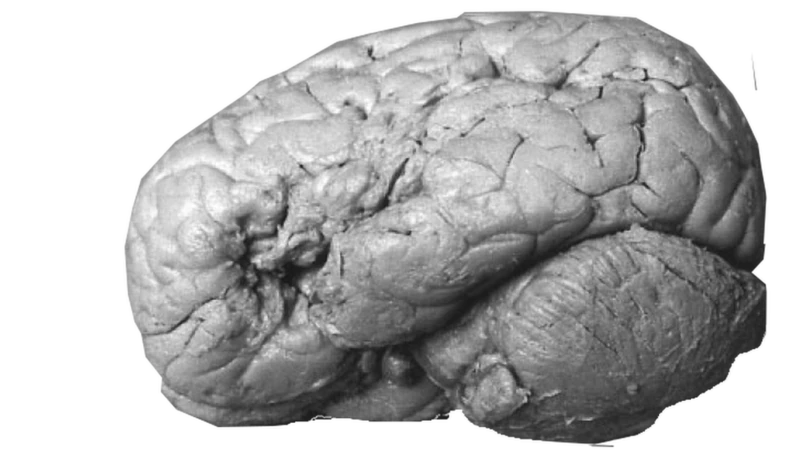

El 17 de abril de 1861, Leborgne falleció a los 51 años. La autopsia reveló un hallazgo decisivo: una lesión extensa en la parte posterior del giro frontal inferior del hemisferio izquierdo del cerebro.

Esa región, que más tarde sería conocida como el área de Broca, se convirtió en el primer indicio sólido de que una zona específica del cerebro estaba directamente vinculada con la producción del lenguaje. El cerebro de Leborgne fue conservado y aún hoy forma parte de colecciones científicas en París.

En 2007, gracias a técnicas modernas de resonancia magnética, un equipo liderado por Nina Dronkers, de la Universidad de California en Davis, volvió a analizar los cerebros de Leborgne y Lelong.

Detectaron daños en el fascículo longitudinal superior, una red de fibras que conecta distintas áreas relacionadas con el lenguaje. El hallazgo permitió concluir que la afasia de Broca está asociada a lesiones más amplias de lo que se pensaba originalmente.